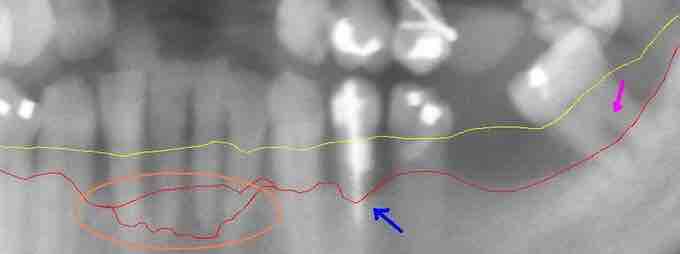

Extensive periodontal disease

This section from a panoramic x-ray film depicts the teeth of the lower left quadrant, exhibiting generalized severe bone loss of 30–80%. The red line depicts the existing bone level, and the yellow line depicts where the gingiva was originally (1–2 mm above the bone), prior to the patient developing periodontal disease. The pink arrow, on the right, points to a furcation involvement, or the loss of enough bone to reveal the location at which the individual roots of a molar begin to branch from the single root trunk; this is a sign of advanced periodontal disease.